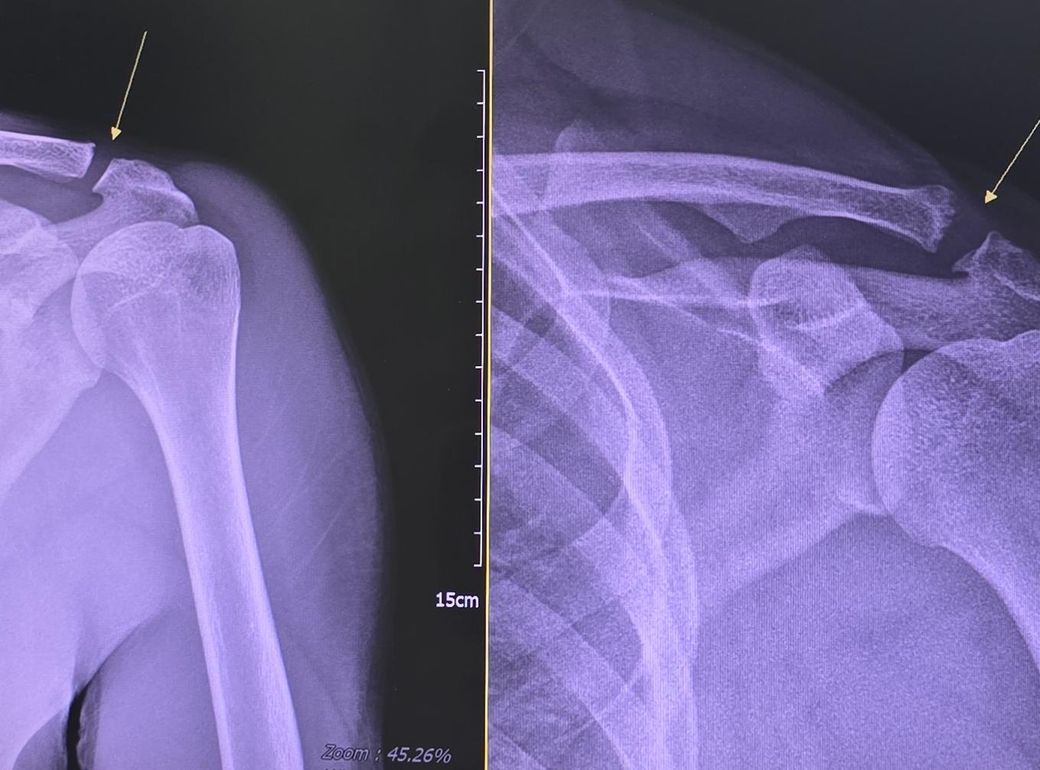

견봉쇄골관절 문의드립니다. 수술해야 하나요?

왼쪽 사진이 18년도에 찍은 사진입니다

정상일 때 사진이고요.

다행히도 자료가 있었네요.

오른쪽 사진이 최근 사진입니다

통증이 있어서 병원을 가서 촬영을 했는데

모양이 달라졌습니다.

수술하지 않고 예전 사진처럼 회복이 가능한가요?

아니면 지금이라도 빨리 수술하는게 좋은 선택일까요?

운동할 때 통증을 느낍니다

가벼운 무게로 하면 괜찮아요.

일상 생활에 큰 불편함은 없습니다.